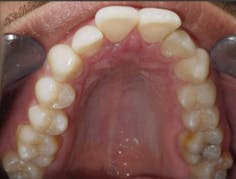

Case 1: 27-year-old male: 2-year clear aligner treatment. There was an estimated 8 mm to 10 mm increase in the transverse measurement. Case and photos courtesy of Dr. Daniel Noor.

Before: V-shaped arch. After: U-shaped arch.